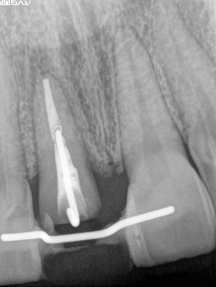

右写真は部分矯正中の装置が入ったレントゲン

治療途中の特別な痛みはありません。